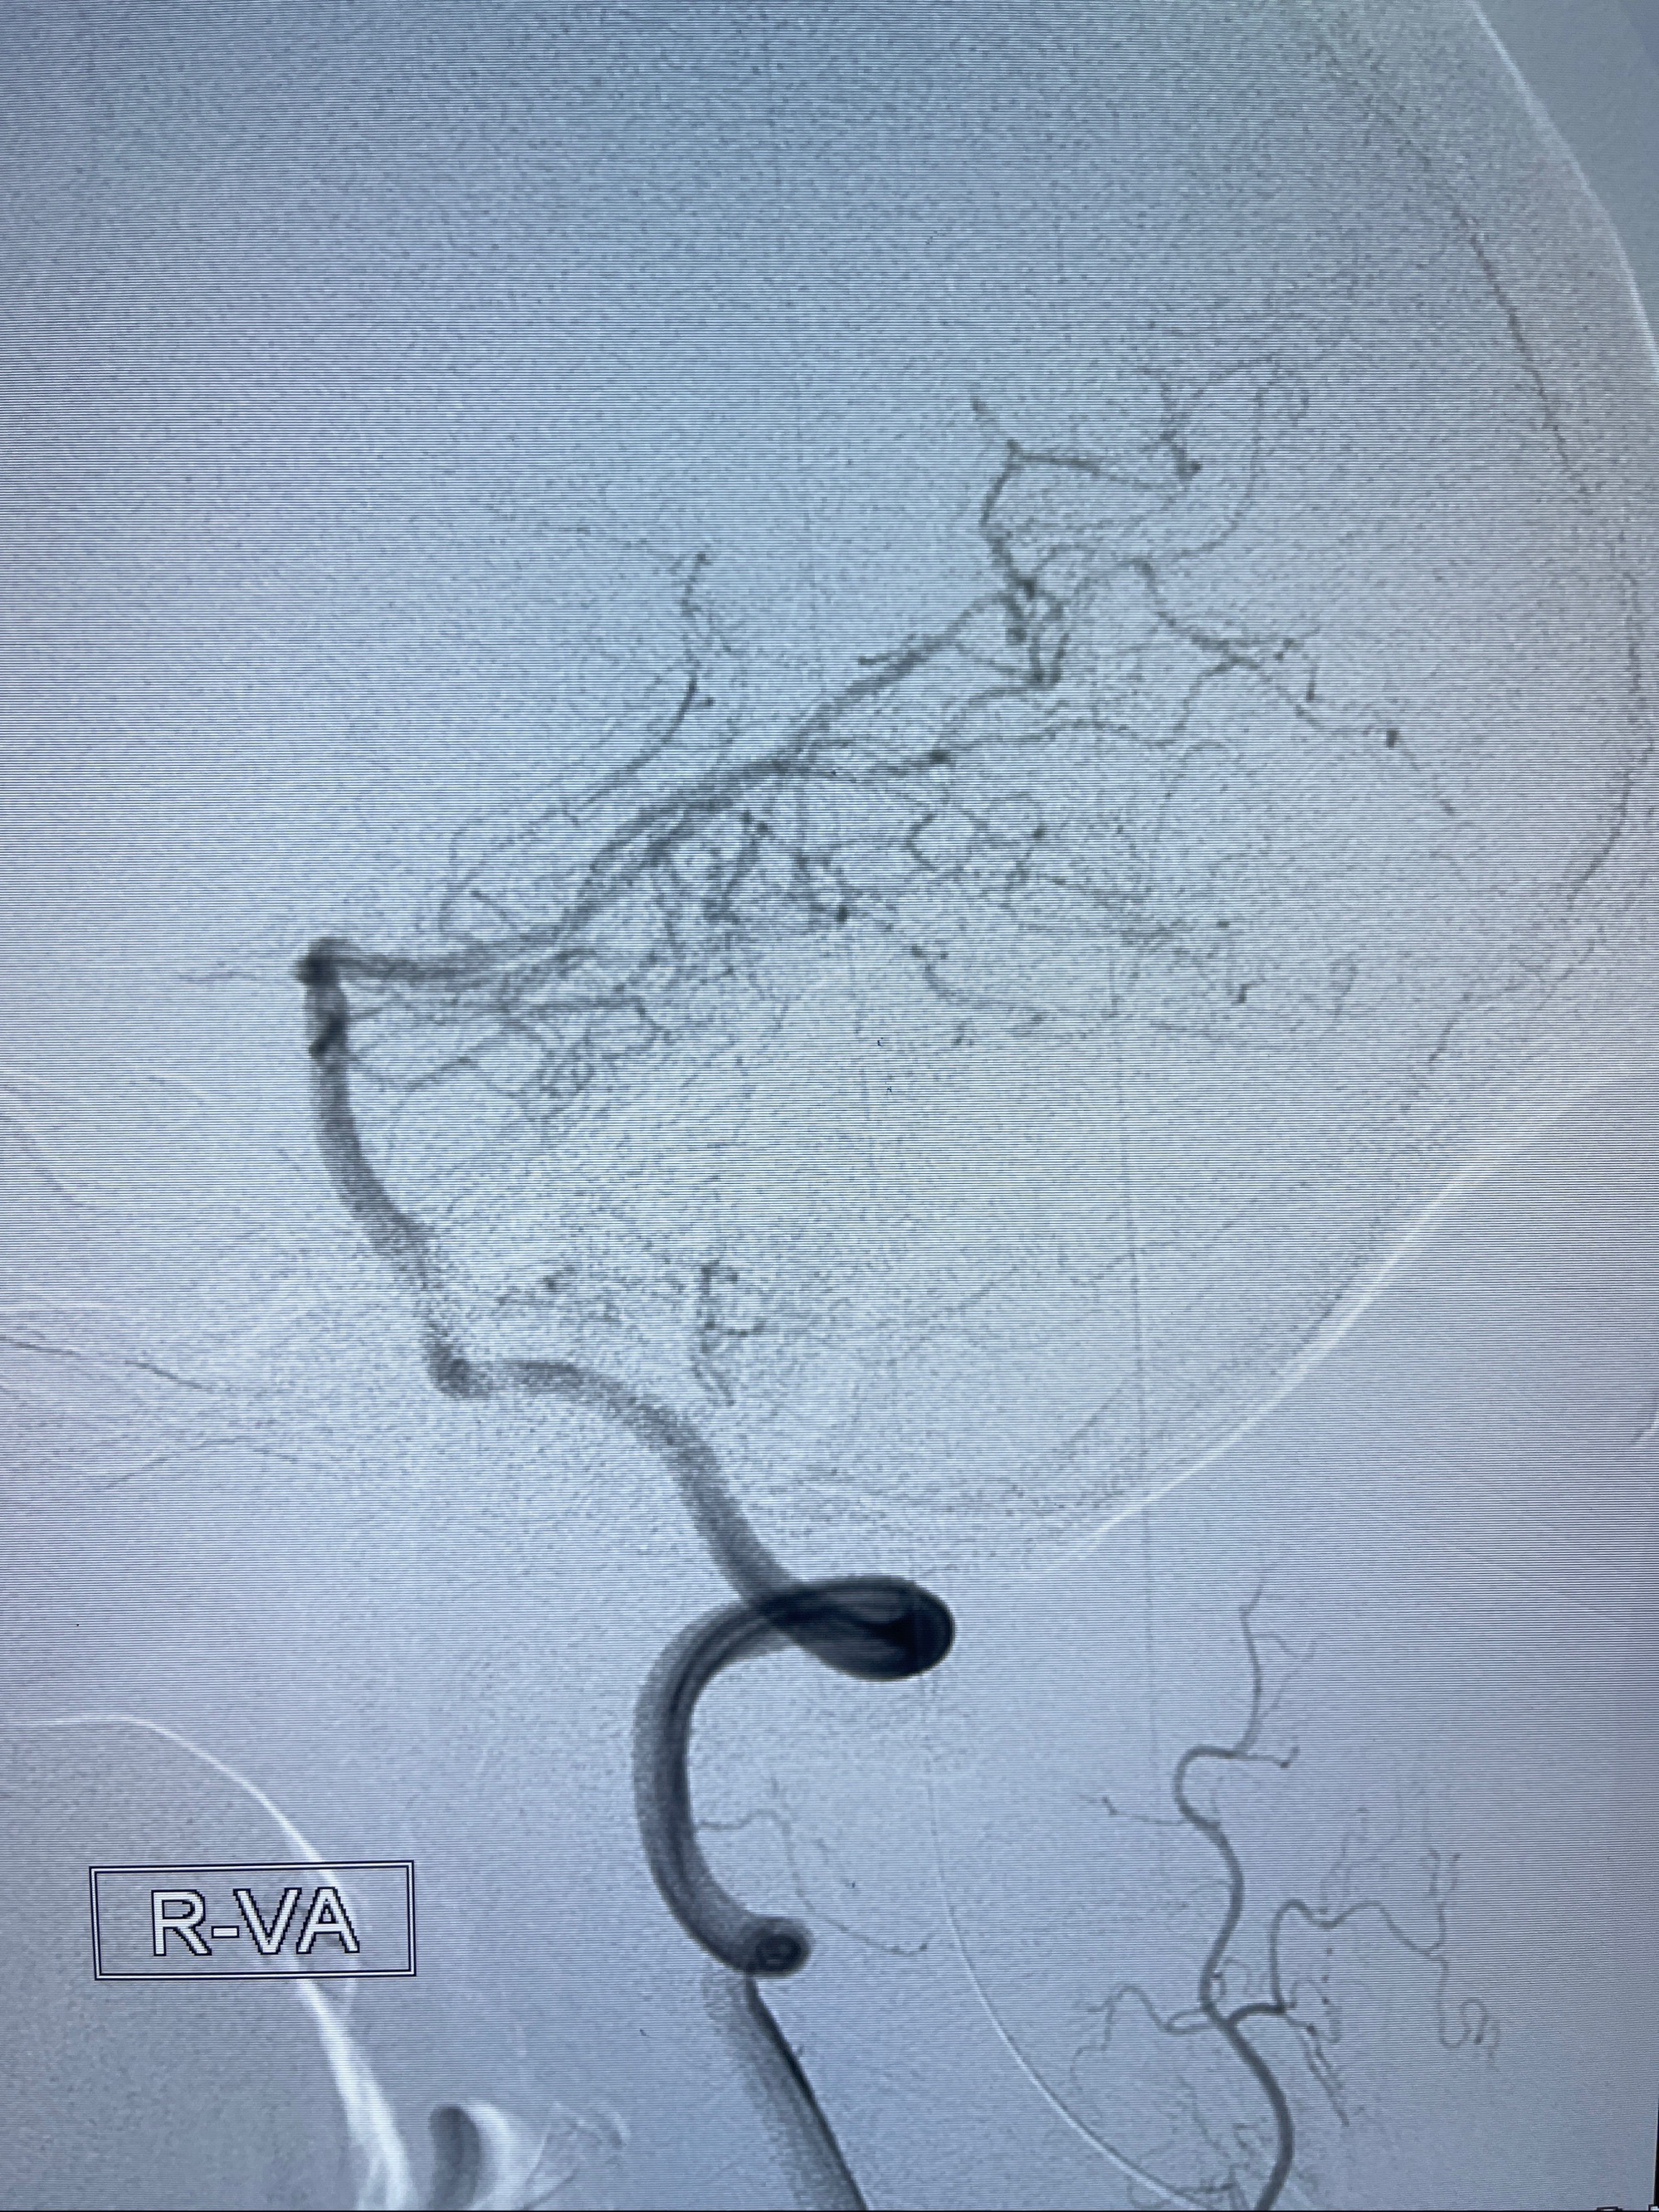

2023-08-14DSA:

左侧大脑中动脉动脉瘤,约2.6-2.8-3.4-2mm大小(瘤颈部、瘤体部、瘤高)